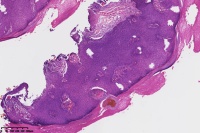

汗孔瘤?

性别

女

年龄

50岁

足底丘疹

汗孔瘤。